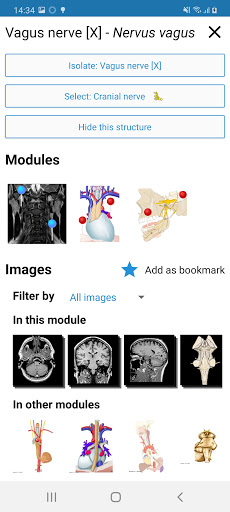

* تحسين عرض التفاصيل للأجزاء التشريحية لتسهيل التعرف عليها في صور الوحدات الحالية والوحدات الأخرى.

- يتم الآن عرض المصطلحات المتعلقة بالهيكل التشريحي في عرض التفاصيل - تمت إضافة

- "التصفية حسب" ، في عرض التفاصيل ، يمكنك الآن تصفية الصور التي تحتوي على الهيكل التشريعي حسب الطريقة

- "التصفية حسب" ، في عرض التفاصيل ، يمكنك الآن تصفية الصور التي تحتوي على الهيكل التشريعي حسب الطريقة